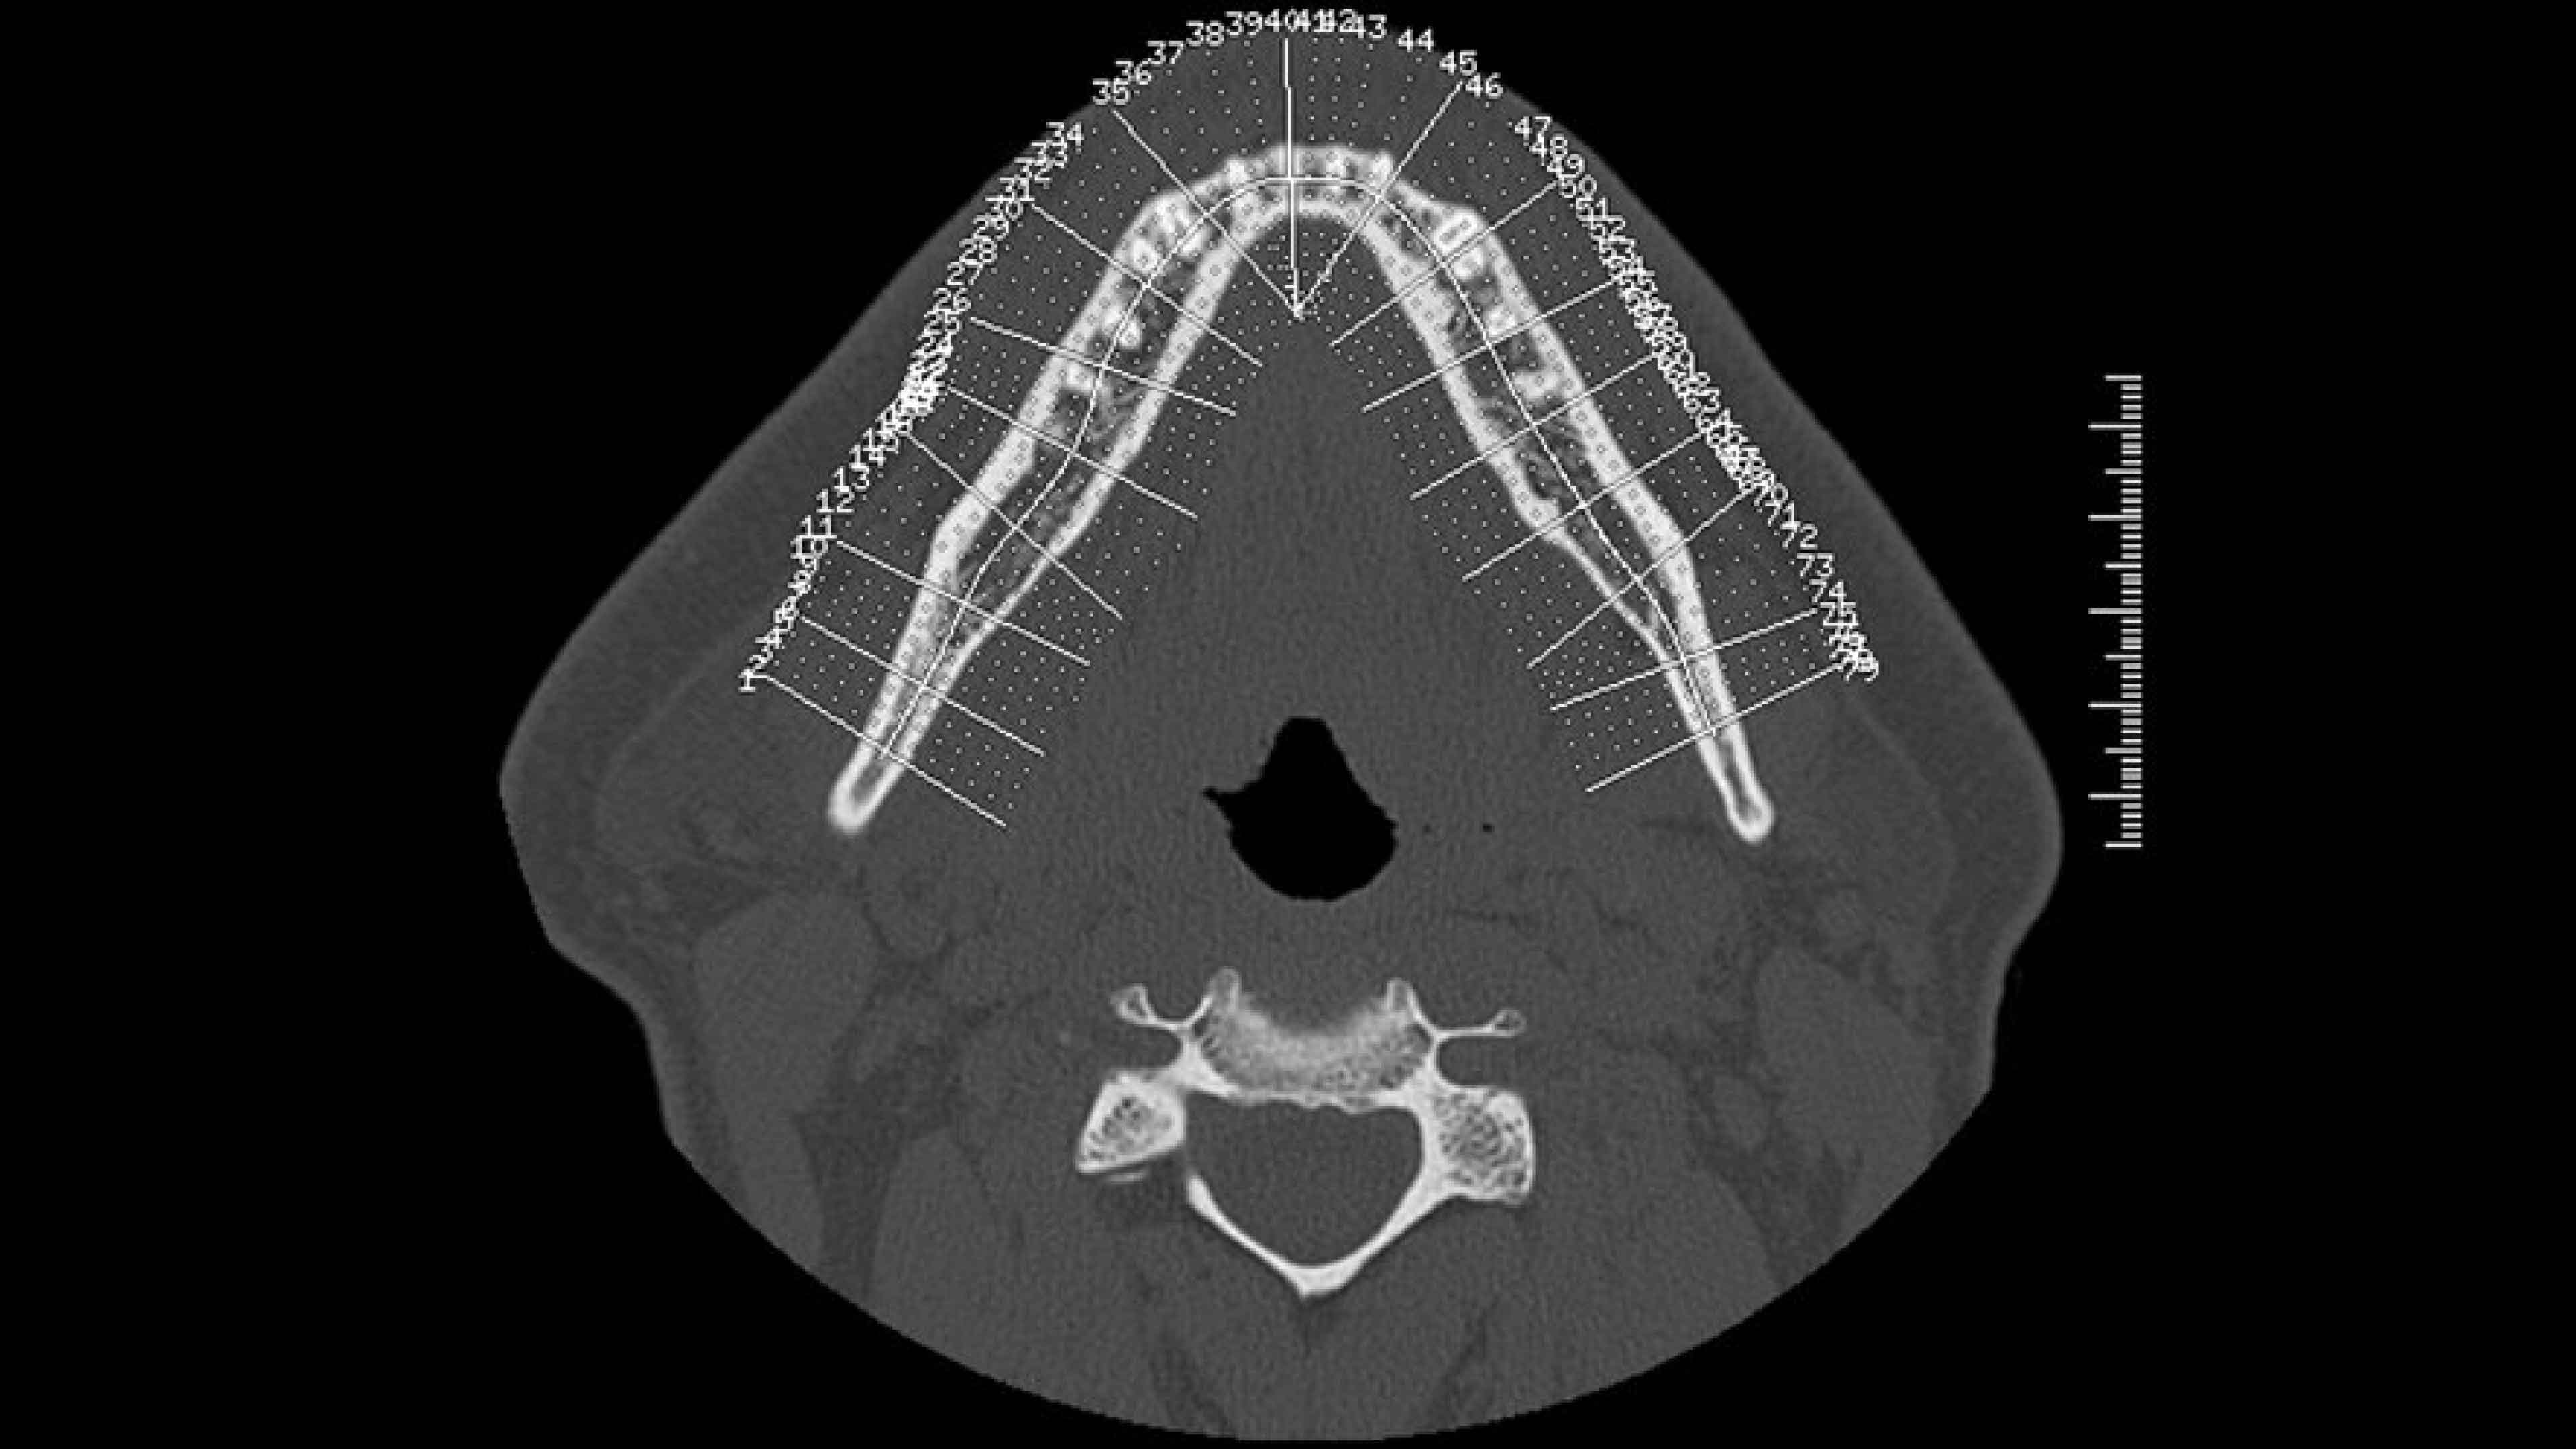

• The curve used to generate panorex and oblique views is drawn on selected axial views. It can be adjusted or redrawn easily at any time during Dentascan procedures.

• Axial panorex and oblique views remain cross referenced on the screen. Oblique views are generated in real time when the cursor is moved on axial or panorex views. A similar feature exists when the cursor is moved on a panorex or oblique view.

• A mm-scale is printed on the side of oblique and panorex views for direct measurement from film. The entire study is annotated to assist in film interpretation.